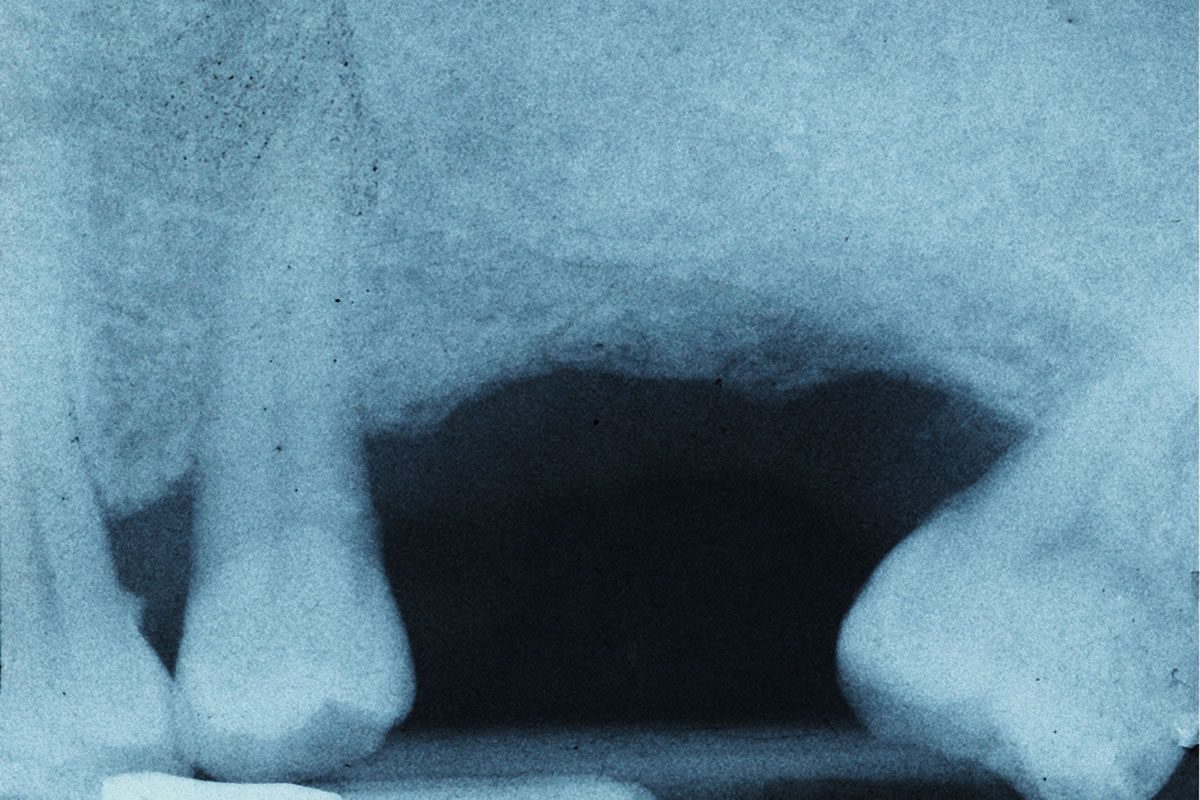

If you’ve lost one or more teeth, a prosthodontist might choose a bridge as the best tooth replacement method for your case. A bridge is one or more crowns linked together to create a single unit. This bridge then gets fixed to the healthy teeth on either side of the gap. The appearance is that of healthy teeth with no gaps or missing teeth. Keep in mind that with bridges, you need to follow special care instructions and have them cleaned regularly.